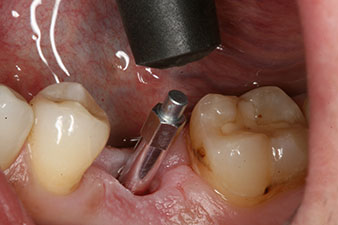

Tras la extirpación minuciosa del tejido de granulación, se incorporó el implante tal como se había planificado (blueSky, bredent).

El torque en el momento de la carga mecánica fue de 43 Ncm. Asimismo, después de atornillar un poste de medición especial adaptado al sistema de implante (SmartPeg), el valor ISQ se determinó con la sonda del módulo Osstell ISQ de W&H.

Este módulo Osstell ISQ que se encuentra disponible como accesorio para la unidad Implantmed de W&H y se acopla al motor de implantes (véase figura 11). El valor ISQ adimensional fue de 64 justo en el momento de la inserción en la dirección bucovestibular y de 68 en la dirección mesiodistal (valor máximo = 100).